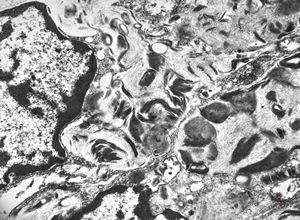

F, 1m. | sepsis - mycotic dermal lesions

M, 57y. | dermal mycotic lesion

M, 57y. | dermal mycotic lesion … toluidine-blue stained semithin section